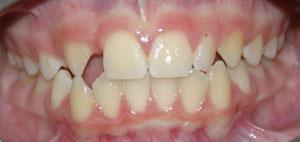

This is a dental condition where one or more teeth are congenitally missing. This is normally a result of genetics and will generally be seen throughout a family over generations. It is important that missing teeth are identified early so that appropriate action can be taken by the orthodontist to either close space as part of orthodontic treatment or maintain space for future replacement. Timing is important as missing teeth lead to adverse movement or ”drift” of adjacent teeth and over-eruption of opposing teeth even as early as age 8 to 10.. Additionally, bone in the area will atrophy over time making future replacement more difficult as the patient ages. This is one reason every child should be seen by an accredited orthodontist by age 6.

Each case is unique and must be attended to on its own merits. Therefore, with respect to the nature of the problem, the space can either be enlarged for tooth replacement, or closed using braces. Tooth replacement options can be in the form of dental implants, or a bridge.